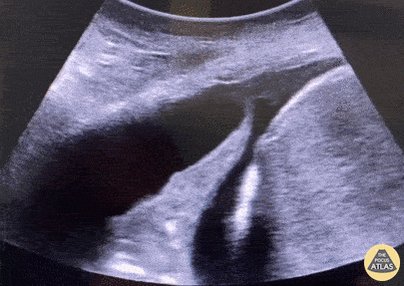

15 - Distended bladder